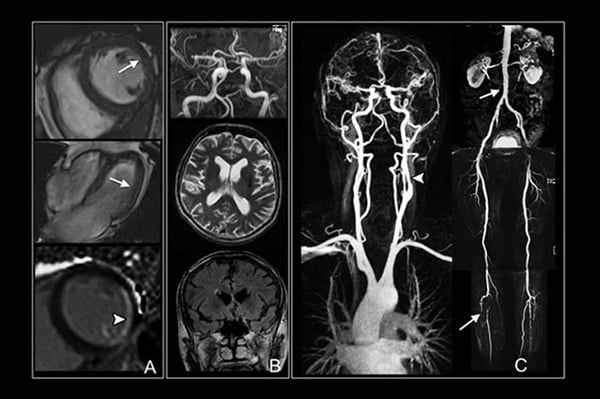

Врачи отмечают, что магнитно-резонансная томография (МРТ) является одним из наиболее безопасных методов диагностики, как с контрастом, так и без него. Однако, несмотря на высокую степень безопасности, существуют определенные показания и противопоказания к проведению этого обследования. МРТ без контраста обычно рекомендовано при подозрении на различные патологии мягких тканей, суставов и головного мозга. В то же время, использование контрастного вещества позволяет более детально визуализировать сосудистые структуры и опухоли, что особенно важно при диагностике онкологических заболеваний.

МРТ считается одним из самых информативных методов диагностики в медицине. Наиболее точные результаты получаются при исследовании внутренних органов, тканей и частей тела, которые содержат много жидкости.

Частые показания к проведению процедуры – подозрения на воспалительные процессы и опухоли (в том числе раковые), патологии кровеносных сосудов, дефекты опорно-двигательного аппарата. Метод почти не применяется для исследования костей скелета при переломах, а также легких, так как эти части тела содержат мало атомов водорода.